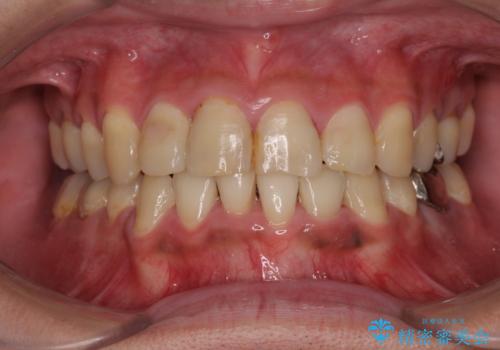

第二小臼歯抜歯の矯正治療は、治療期間が長引くことが多いですが、動きが非常に良く、予定の治療期間で終えることができました。

上下の正中も思っていた以上に良い位置に改善されました。